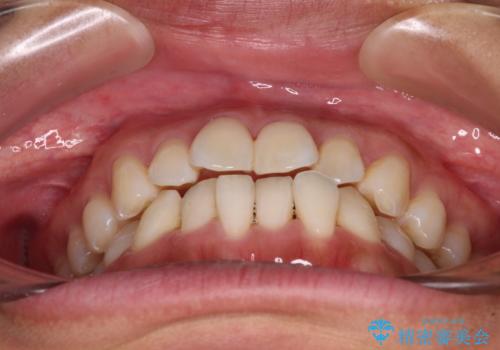

- 前歯のデコボコで前方に出ていることを気にして来院された患者様です。

上顎前歯が捻れて前方に飛び出しており、下顎前歯もそれに沿うようにデコボコとなっていました。

IPR(歯と歯の間を削る処置)によりスペースを獲得して上下顎前歯のデコボコを改善し、飛び出している前歯が引っ込むように設定し、インビザラインにて矯正治療を行うこととしました。